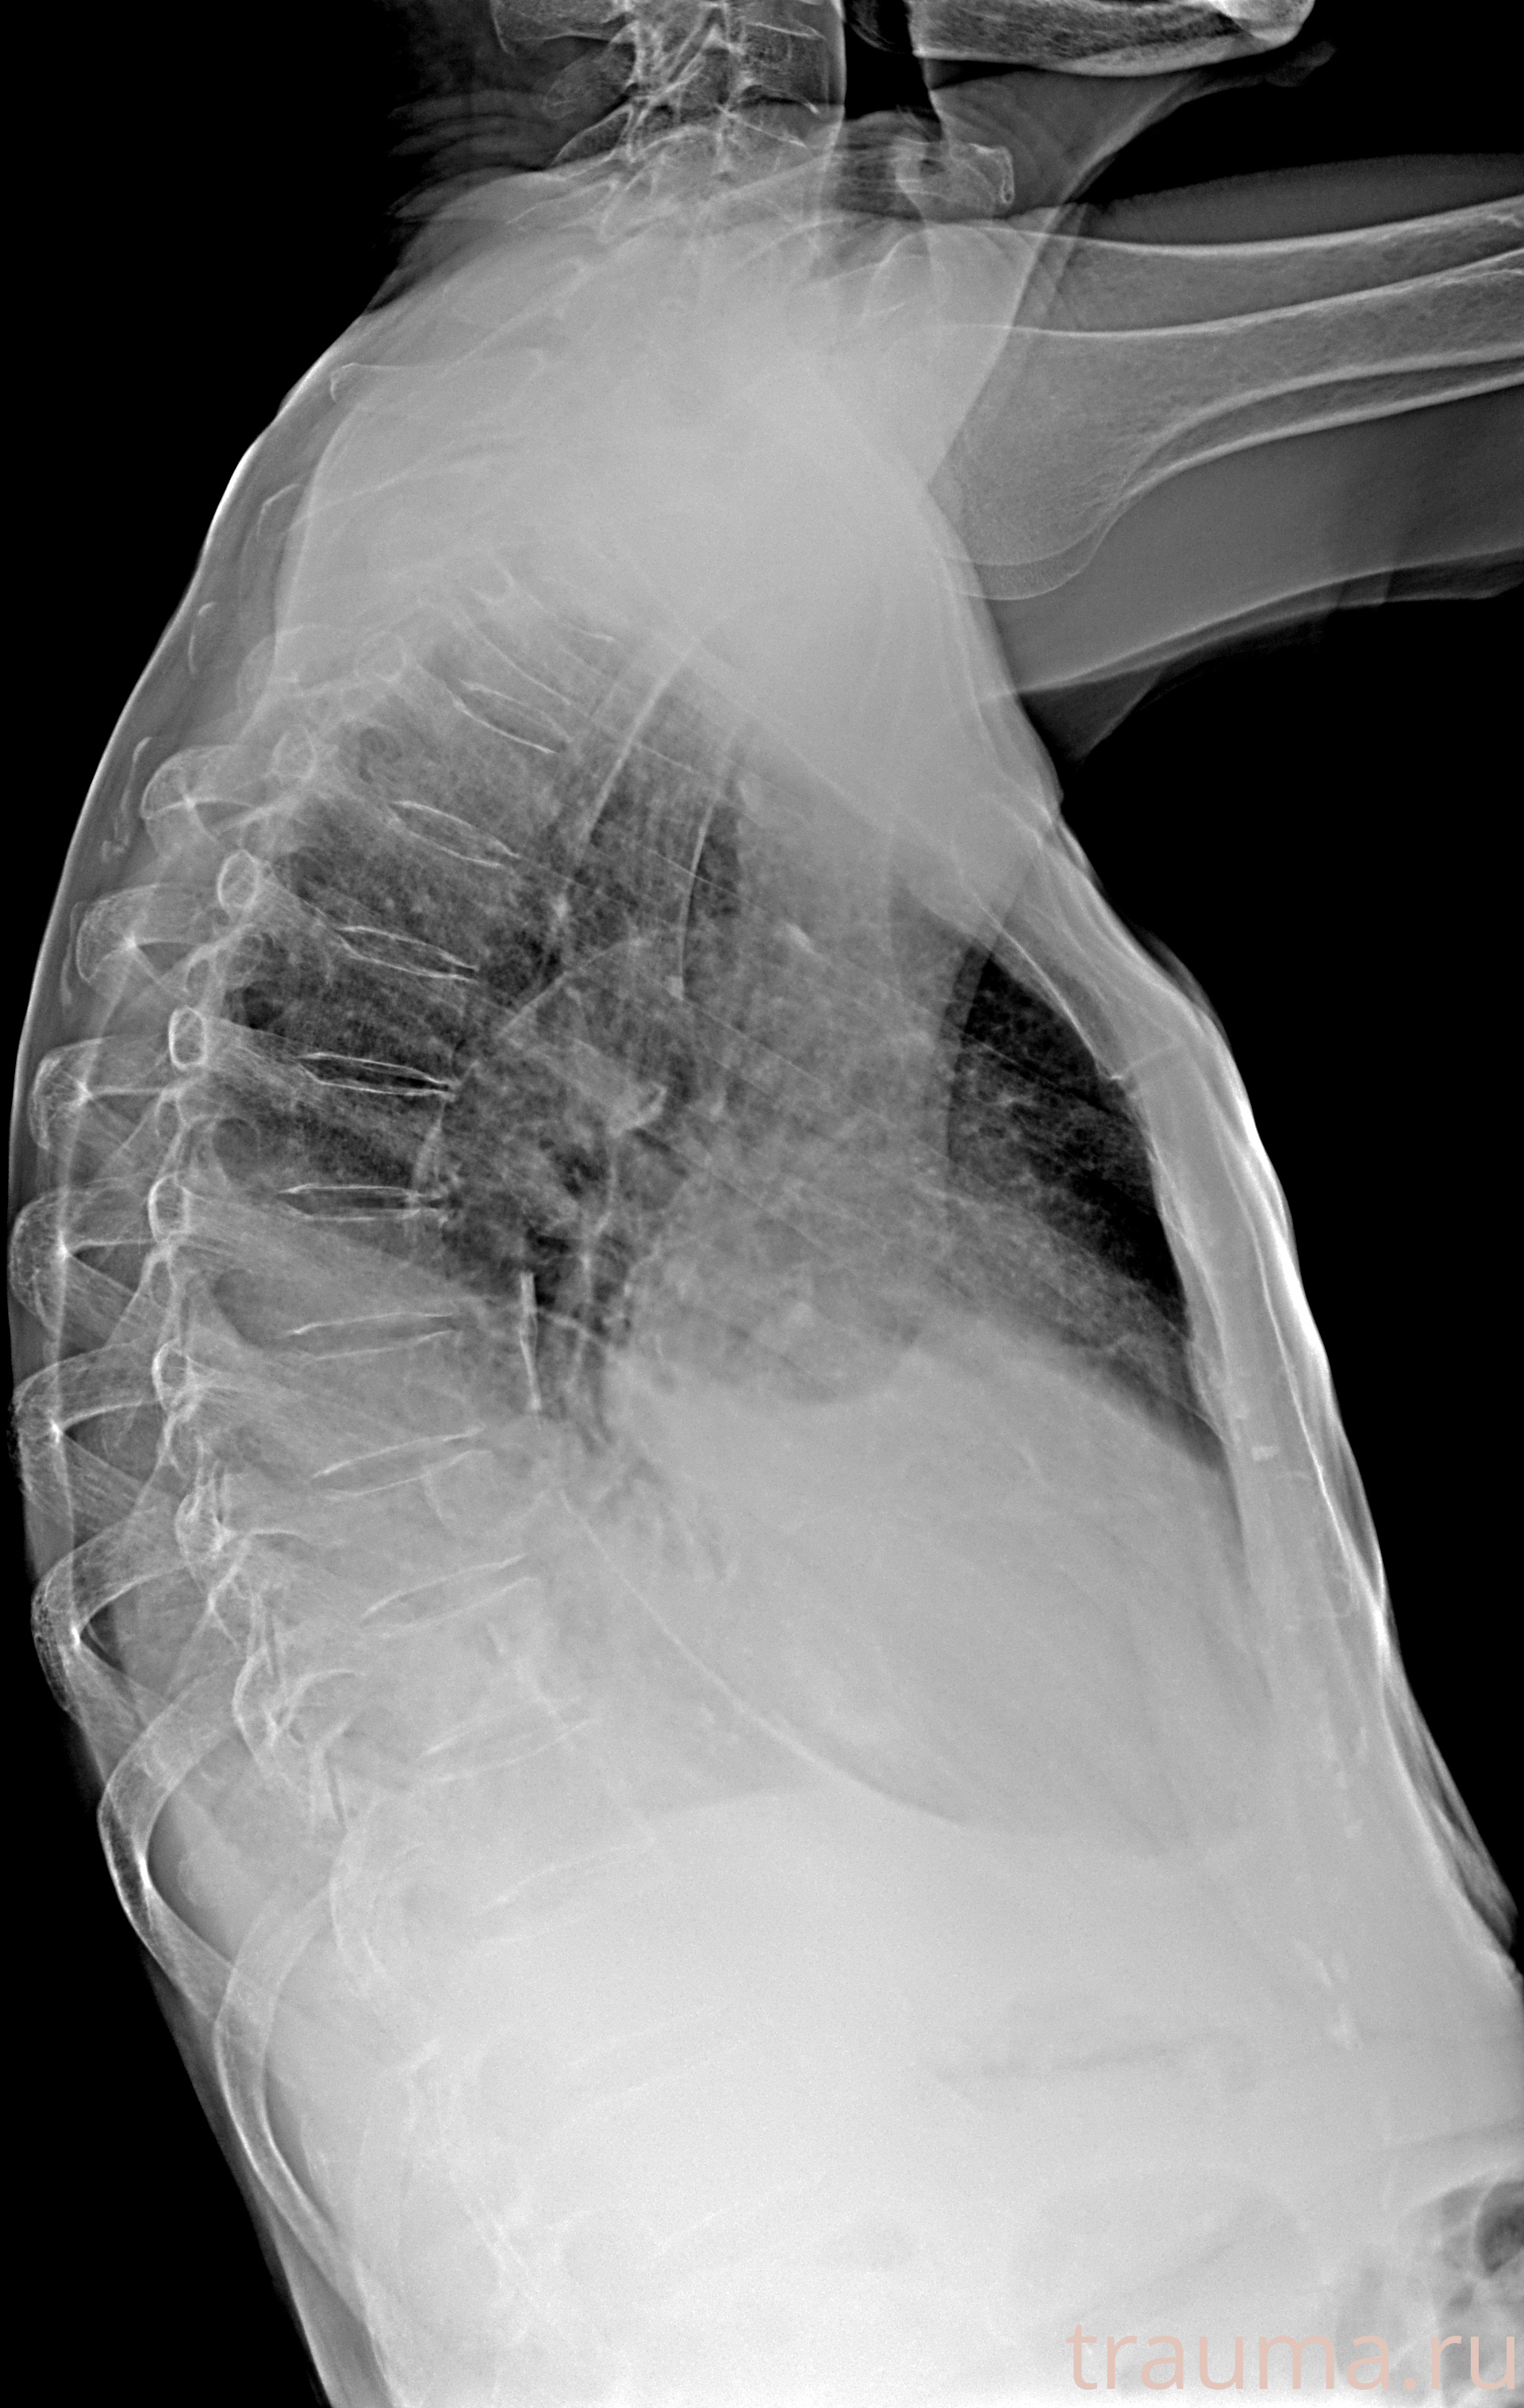

Рентген на дому: по вашему адресу приезжает врач-рентгенолог, травматолог-ортопед с мобильным рентгеновским аппаратом, проводит диагностику травмы или заболевания, делает необходимые рентгенограммы, дает рекомендации по дальнейшему лечению. Получить качественные снимки в домашних условиях возможно благодаря уникальной методике, разработанной МосРентген Центром для института  Склифосовского